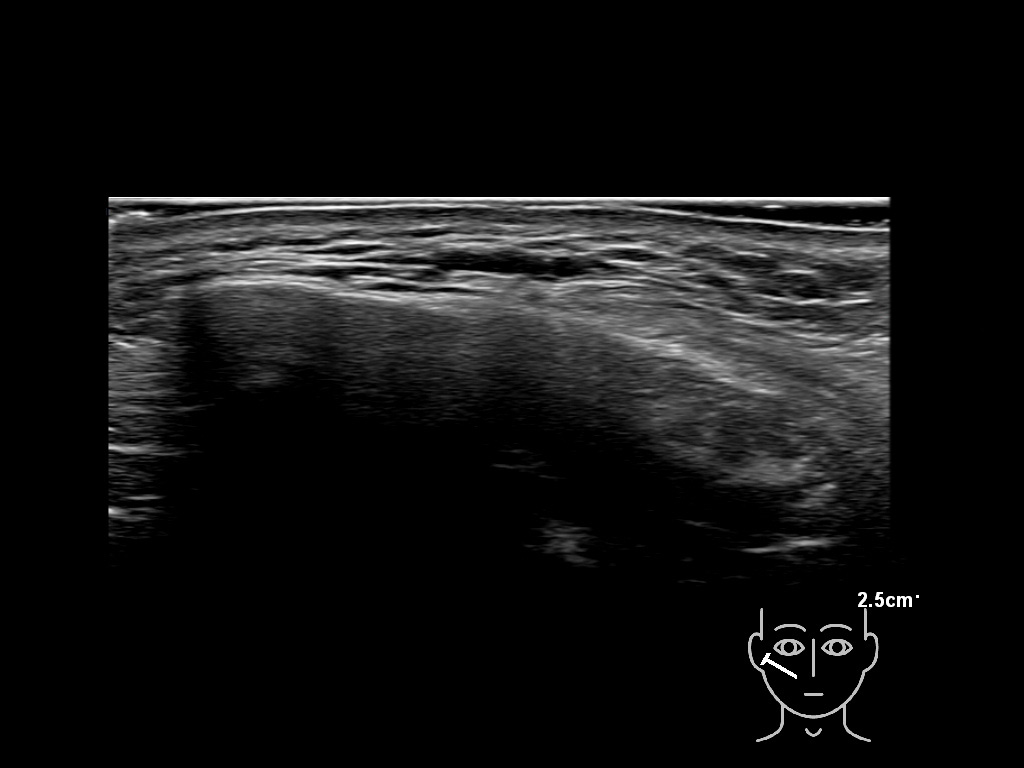

Filler deposits may end up unintentionally in the SMAS or fascial layers of the skin. Very often this will not lead to adverse events, however, adverse events ( nodules, migration / redistribution impaired muscle movement and smiling and malar edema) are are often related to filler ending up in the SMAS or fascia.

Study the first image to recognize the different layers. If you are sure about the layers, swipe to the second image to view the answer (if applicable).